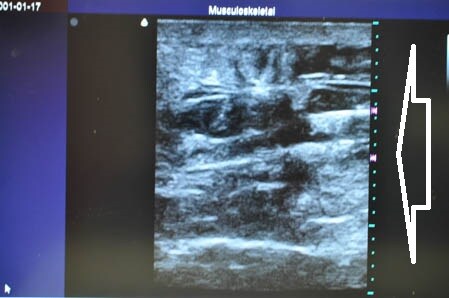

まずはいつものように

3Dタッチビュー(超音波画像)から見てみましょう。

白い矢印部分が皮下脂肪層です。

上腹部から。